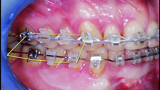

BiTurbo2 system for rapid deep overbite correction